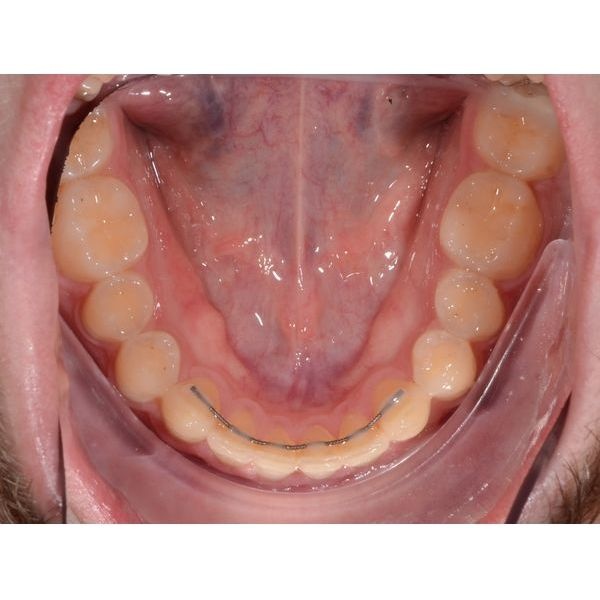

Чтобы сохранить результат, пациенту установили несъёмные ретейнеры (проволочные конструкции, удерживающие зубы в нужном положении) и изготовили индивидуальную ретенционную капу на верхнюю челюсть. Мужчину проинструктировали по поводу режима ношения и уходу за ретенционными аппаратами.